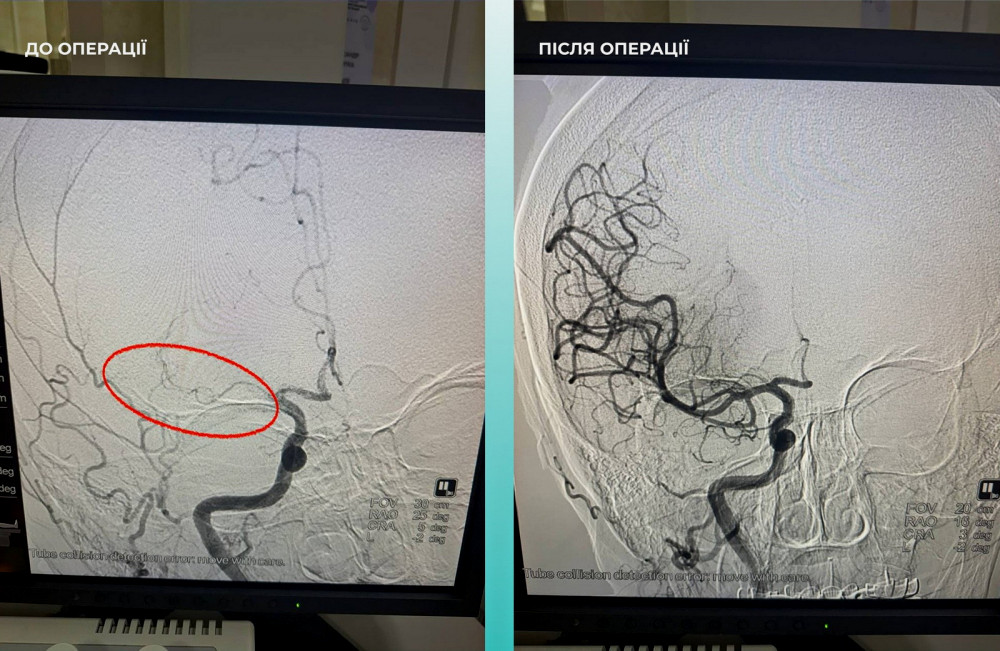

Пациентка, жительница Одессы, была госпитализирована с тяжелым случаем инсульта. Во время компьютерной томографии врачи обнаружили закрытие средней мозговой артерии.

Медицинская команда, состоящая из различных специалистов, приняла сложное, но крайне важное решение провести одновременную тромбоэктомию как мозговой, так и легочной артерий.

Операция прошла успешно. В настоящее время пациентка чувствует себя значительно лучше: она в сознании и уже может двигать конечностями.